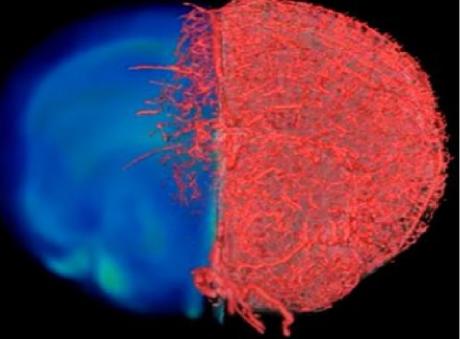

Les chercheurs de Baltimore ont développé et testé une nouvelle approche d'imagerie qui va permettre aux scientifiques de capturer des images de vaisseaux sanguins à différentes échelles spatiales : VascuViz est basé sur un mélange de polymères à prise rapide qui remplir les vaisseaux sanguins et les rend visibles -avec de multiples techniques d'imagerie. Le composé, testé in vitro, puis dans une variété de tissus de souris, par perfusion à travers le système vasculaire de modèles de cancer du sein, dans les muscles des jambes, le cerveau ou encore les tissus rénaux a permis, via l'IRM, la tomodensitométrie et la microscopie optique d’obtenir des visualisations 3D du système vasculaire.

L'approche permet plus globalement aux chercheurs de visualiser avec une grande précision la structure du système vasculaire d'un tissu. Ces données, en conjonction avec un modèle d’intelligence artificielle, des images complémentaires, d’autres biopsies tissulaires, permettent de clarifier le rôle complexe du flux sanguin dans la maladie. Ces images à l’échelle du vaisseau sanguin vont permettre de mieux cerner la biologie des maladies caractérisées par des anomalies du flux sanguin mais également décrypter les structures et les fonctions des différents tissus du corps.

VascuViz surmonte ce problème en rendant la structure des plus grandes artères au micro-vaisseau le plus minuscule visible avec tout un panel de techniques d'imagerie classiques, ce qui permet aux chercheurs d’accéder à une compréhension spatiale de la structure et de la santé des vaisseaux, ainsi que des tissus environnants. VascuViz permet d’estimer plus précisément des caractéristiques telles que le flux sanguin dans les vaisseaux sanguins réels, puis de combiner ces données avec des informations complémentaires, telles que la densité cellulaire. Ainsi, des données obtenues grâce à VascuViz sont ensuite entrées dans des modèles informatiques du flux sanguin,

tels que les modèles développés pour les cancers, ce qui offre une image précise de l’évolution de la maladie.